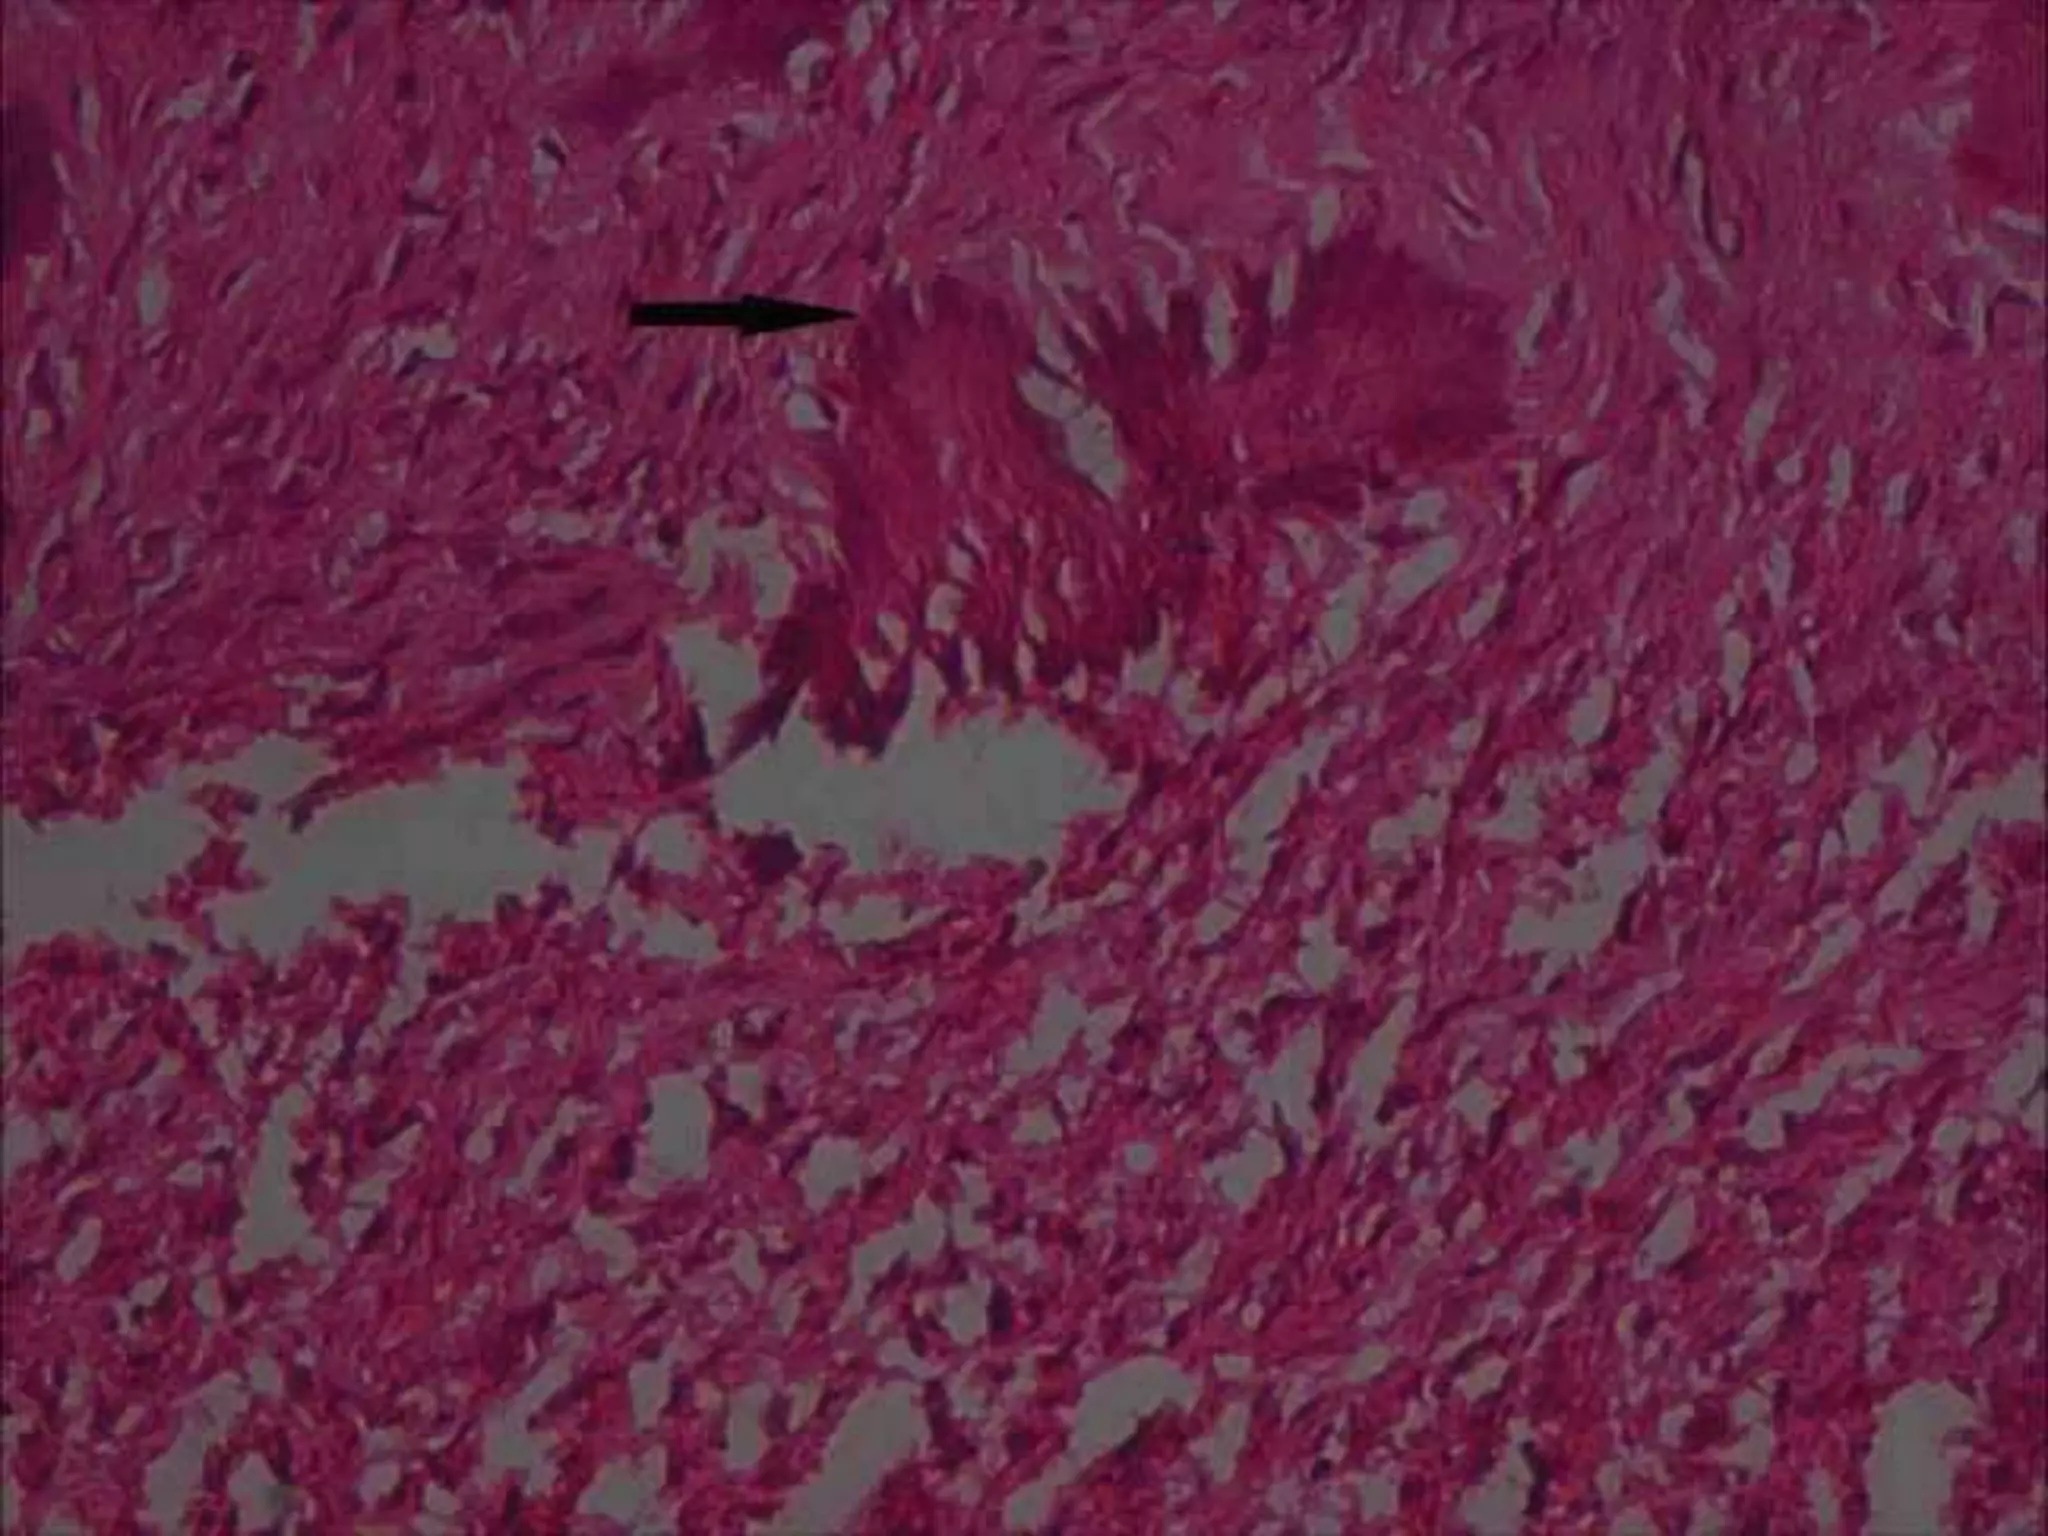

• #20 Golg named these spherical structures as ‘psammoma- like bodies’. These particles vary in appearance such a concentric lamellated to irregular both having central basophilic area and a peripheral eosinophilic fringe. Ultra structure of psammoma- like bodies manifest with a dark rim of crystals. From these crystals spicules and needle-like crystalloids project toward the periphery resembling brush border

• #22 Magnified photomicrograph (40X) of psammoma- like bodies, indicated with an arrow showing peripheral brush border appearance